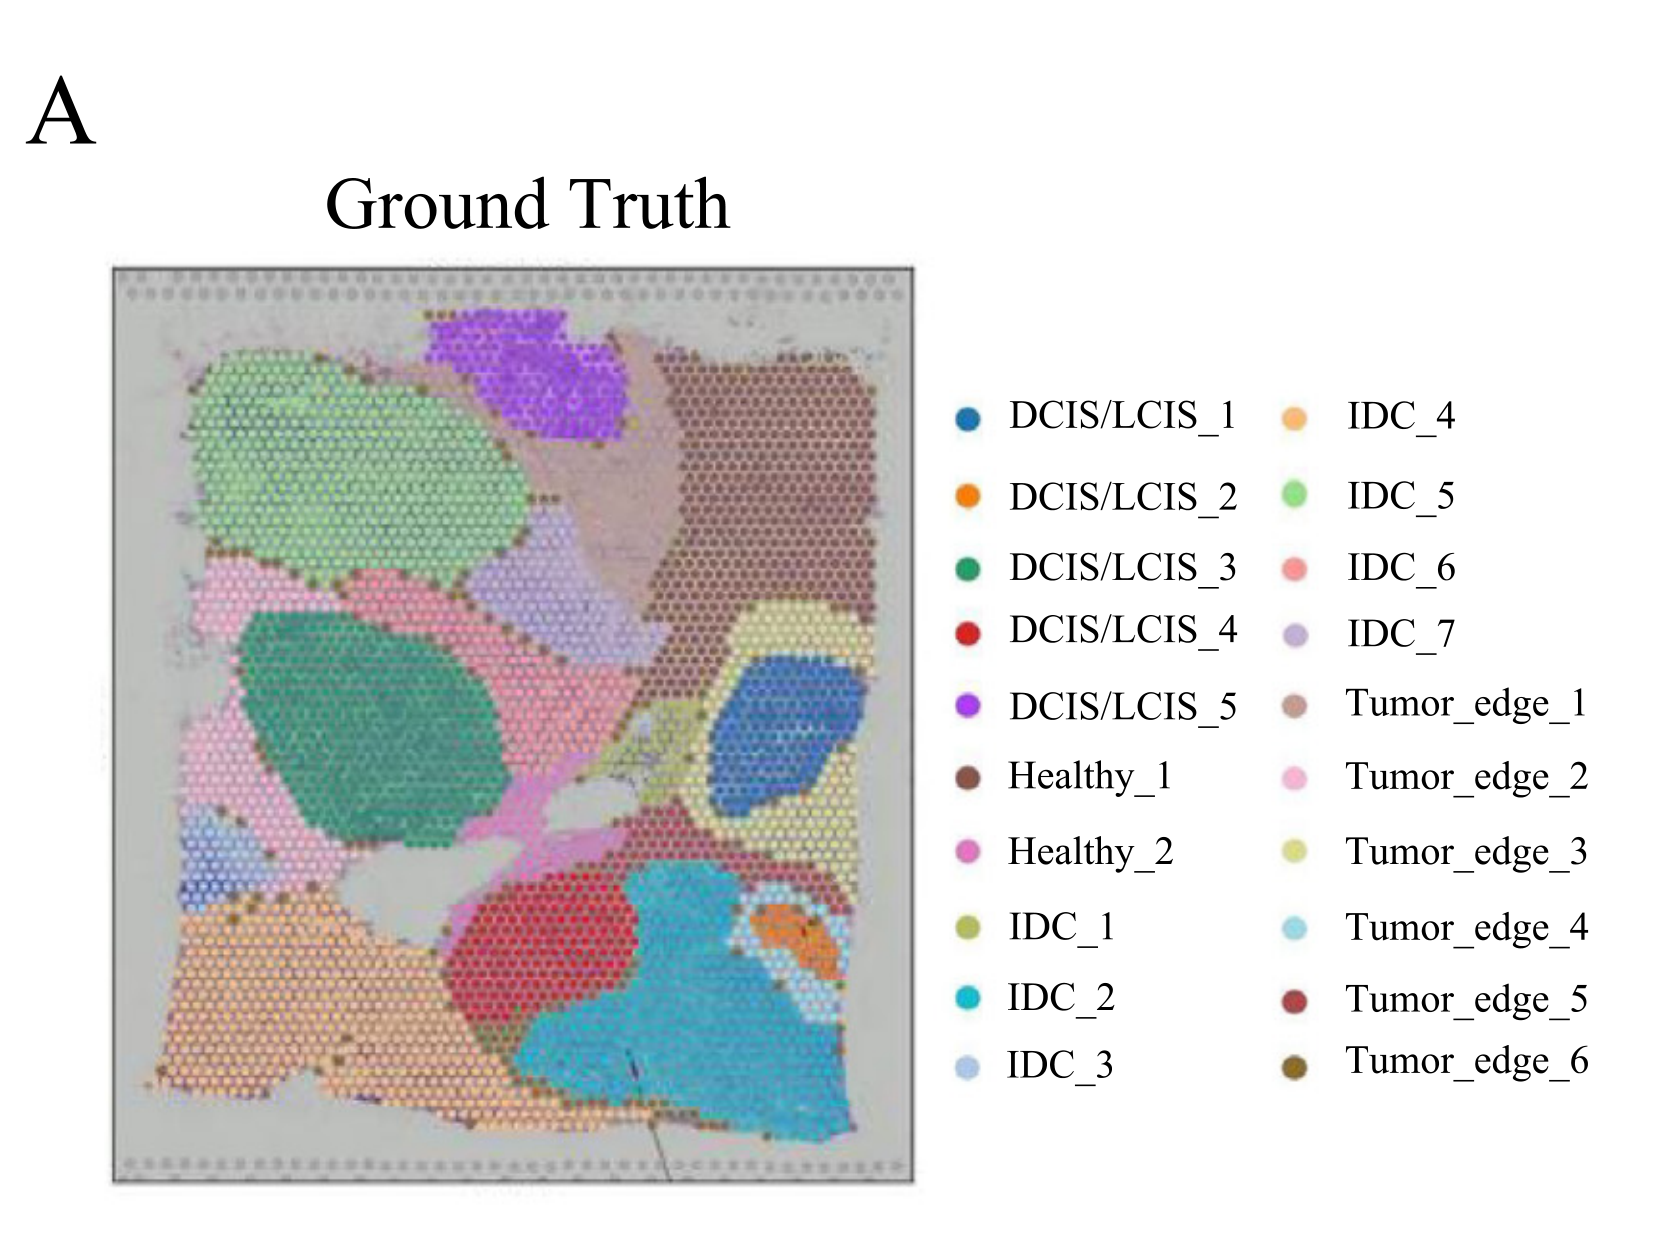

Gui Y. et al. - 2024

Spatial domains identification in spatial transcriptomics using modality-aware and subspace-enhanced graph contrastive learning

Condition Dimension

N/A

Data Components

Biological AnnotationGene Expression Matrix

Metadata

None

Modality

Imaging-based

Resolution of observation

Field of view

Visualized Elements

FeatureStatistic

Biological

Molecular

Abstraction

Complete

Chart Type

Dot Chart

Communicative/Contextualization

Highlighting

Comparative Design

Explicit encoding

Layout

Linear

Scalability Strategy

Sampling/FilteringSummay/Aggregate

Which genes most specifically mark each spatial tissue domain, and how prevalent and highly expressed are they within their domain?